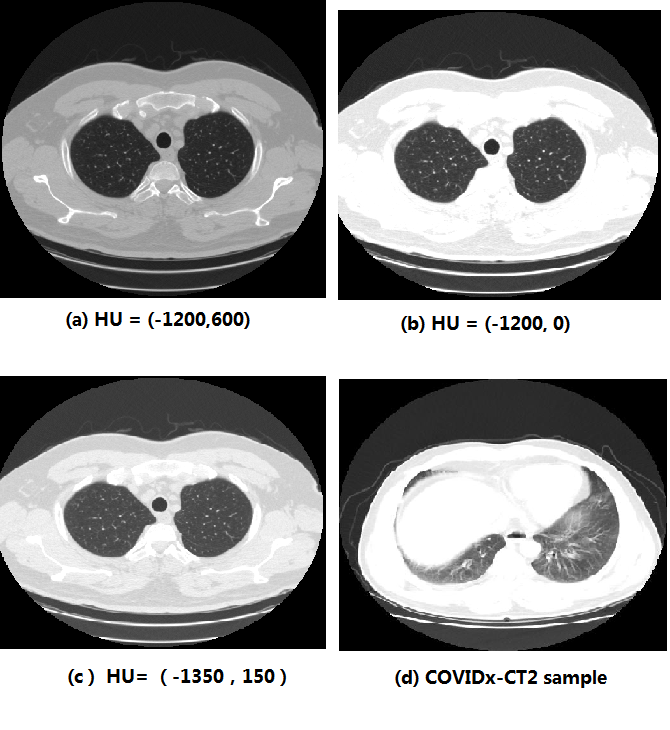

We present an automatic COVID1-19 diagnosis framework from lung CT images. The focus is on signal processing and classification on small datasets with efforts putting into exploring data preparation and augmentation to improve the generalization capability of the 2D CNN classification models. We propose a unique and effective data augmentation method using multiple Hounsfield Unit (HU) normalization windows. In addition, the original slice image is cropped to exclude background, and a filter is applied to filter out closed-lung images. For the classification network, we choose to use 2D Densenet and Xception with the feature pyramid network (FPN). To further improve the classification accuracy, an ensemble of multiple CNN models and HU windows is used. On the training/validation dataset, we achieve a patient classification accuracy of 93.39%.